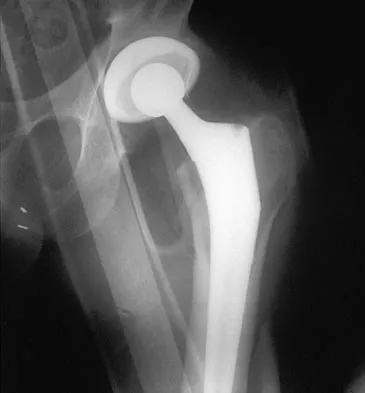

A 45-year-old man reports right shoulder pain with overhead activities only. Figures 47a through 47d show the radiographs, bone scan, and MRI scan of a lesion of the proximal shoulder. What is the most appropriate treatment?

The figures show a lesion of the proximal humerus consistent with an enchondroma. The lesion is calcified on the radiographs. There is no cortical destruction, significant endosteal scalloping, or soft-tissue mass. The bone scan shows mild uptake in the area of the proximal humerus, and the T2-weighted MRI scan shows a lesion with high uptake, suggesting a lesion with high water content. A CT scan could also be obtained to rule out bone destruction or periosteal reaction. Pain with overhead activities is likely related to the rotator cuff. A biopsy is unlikely to add information because of inherent difficulties interpreting low-grade cartilaginous lesions. Curettage and grafting and en bloc resection are excessive treatments for a benign lesion that is apparently asymptomatic. Observation with a follow-up radiograph in 3 to 6 months is appropriate. Menendez LR (ed): Orthopaedic Knowledge Update: Musculoskeletal Tumors. Rosemont, IL, American Academy of Orthopaedic Surgeons, 2002, pp 103-111.